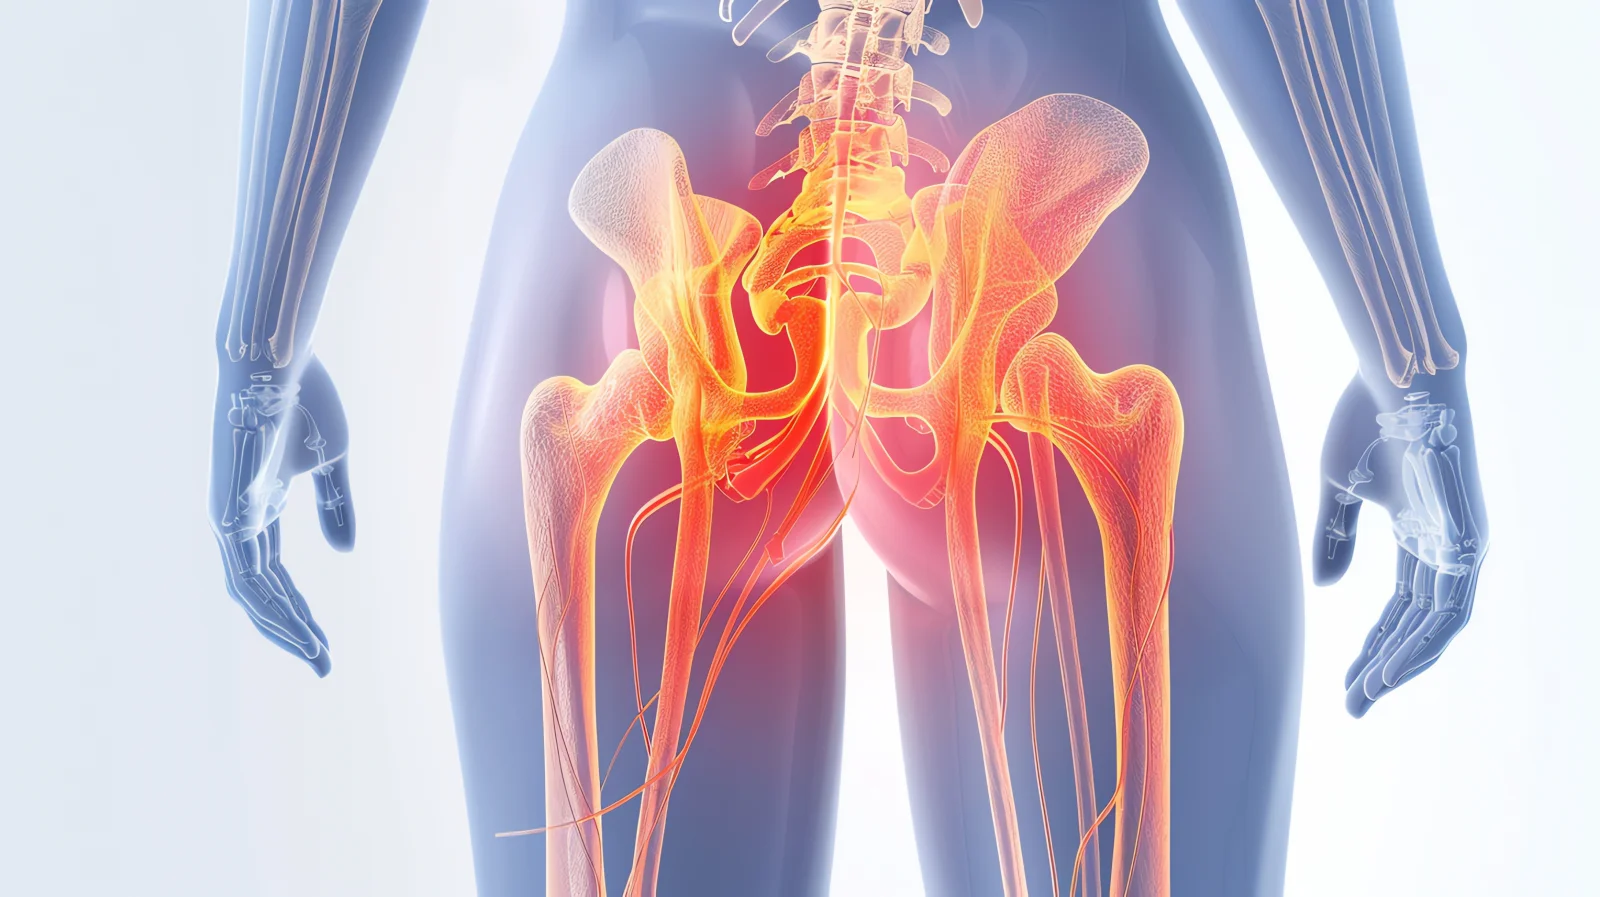

Total Hip Replacement is a surgical procedure used to replace a damaged hip joint with an artificial implant. It is commonly performed when severe hip pain and stiffness interfere with daily activities.

Total Hip Replacement is a procedure in which the damaged parts of the hip joint are removed and replaced with artificial components to restore joint movement and relieve pain.